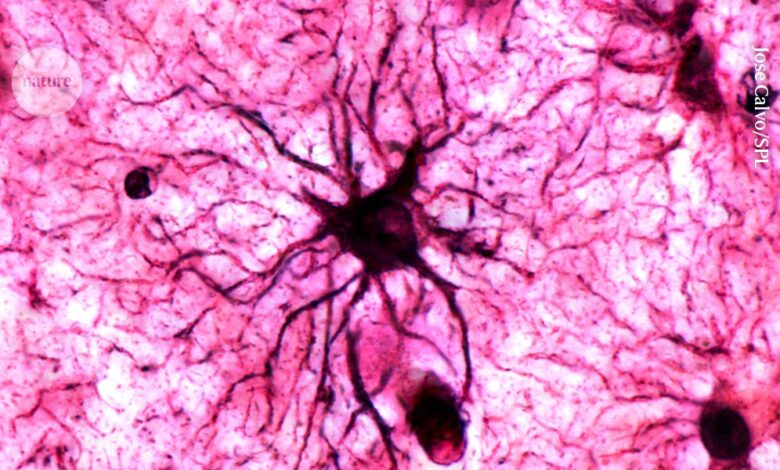

يلعب نوع من خلايا الدماغ يسمى الخلايا النجمية دورًا حاسمًا في تثبيت الذكريات في الدماغ.الائتمان: خوسيه كالفو / SPL

لماذا نحن قادرون على تذكر الأحداث العاطفية بشكل جيد؟ وفقا لدراسة نشرت اليوم في طبيعة1, نوع من خلية في الدماغ تسمى الخلايا النجمية هو لاعب رئيسي في تثبيت الذكريات للاستدعاء على المدى الطويل.

كان يعتقد أن الخلايا النجمية ببساطة دعم الخلايا العصبية في خلق الآثار الجسدية للذكريات في الدماغ، لكن الدراسة وجدت أن لها دورًا أكثر نشاطًا، ويمكن حتى أن يتم تحفيزها بشكل مباشر من خلال التجارب العاطفية المتكررة. ويشير الباحثون الذين يقفون وراء هذه النتيجة إلى أن الخلايا يمكن أن تكون هدفًا جديدًا لعلاج حالات الذاكرة مثل تلك المرتبطة باضطراب ما بعد الصدمة ومرض الزهايمر.